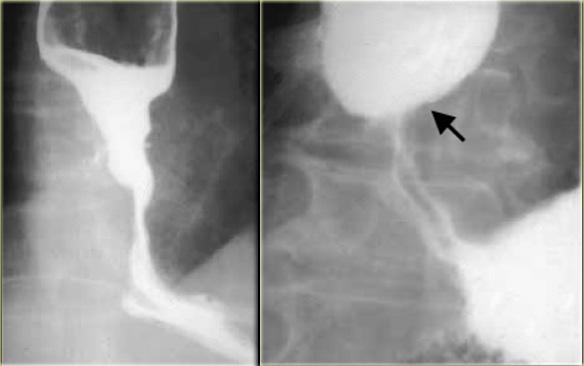

Kế bên là hình ảnh bệnh nhân ung thư có hẹp thực quản giống co thắt tâm vị.

Bệnh lý ác tính đoạn thực quản xa có thể rất giống co thắt tâm vị.

Nếu nhu động thực quản bình thường, có thể loại trừ co thắt tâm vị.

Tuy nhiên, nếu bất thường, các đặc điểm hình ảnh tinh tế như: hẹp không đối xứng, không đều, đột ngột hoặc ở vị trí cao, bất thường niêm mạc, hoặc bất thường cố định sẽ gợi ý chẩn đoán.

Bên trái là một trường hợp giả co thắt tâm vị khác.

Hẹp đoạn xa mô phỏng co thắt tâm vị, nhưng vị trí hẹp lệch tâm, các bờ vai không đối xứng (mũi tên), và niêm mạc không đều tại đỉnh vùng hẹp.

CT cho thấy thành đáy vị dày lên (mũi tên) do ung thư biểu mô tuyến.